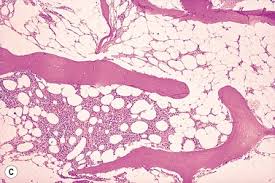

Pure Red Cell Aplasia : In this disease, the bone marrow becomes unable to develop red blood cells.. It is characterized by normocytic, normochromic anemia, associated with reticulocytopenia in the peripheral blood and absent or infrequent erythroblasts in the bone marrow.1. Prca occurring secondarily to medications and infections is pure red cell aplasia is characterized by maturation arrest in the formation of erythrocytes. Acquired pure red cell aplasia: Pure red cell aplasia is often associated with thymomas, and is cured in a quarter of cases by thymectomy (jacobs et al., 1959). However, white blood cell and platelet production are normal.

Pure red cell aplasia is characterized by anemia, reticulocytopenia and diminished bone marrow erythroid precursors. Pure red cell aplasia (prca) is a syndrome defined by a normocytic normochromic anemia with severe reticulocytopenia and marked reduction or absence of erythroid precursors from the bone marrow. However, white blood cell and platelet production are normal. Pure red cell aplasia is an uncommon disorder. Pure red cell aplasia (prca) or erythroblastopenia refers to a type of anemia affecting the precursors to red blood cells but not to white blood cells. Pure red blood cell aplasia (prca) is an uncommon condition that results due to a defect in the bone marrow. Erythroblasts which give rise to rbcs are almost. Acquired pure red cell aplasia: Pure red cell aplasia is a rare form of anemia caused when the bone marrow stops producing red blood cells, but produces white blood cells normally. Refers to a rare type of anaemia affecting precursors of. It is usually a symptom of another underlying disorder, but can be congenital or ideopathic. A rare blood cell disorder where there is a sudden decrease in the number of red blood cells (erythrocytes) produced by the. Pure red cell aplasia (prca) is a rare bone marrow failure syndrome defined by a progressive normocytic anaemia and reticulocytopenia without pure red cell aplasia (prca), initially described by kaznelson in 1922 1, is a rare disorder, characterized by the presence of a severe normochromic.

Pure red cell aplasia is often associated with thymomas, and is cured in a quarter of cases by thymectomy (jacobs et al., 1959). Erythroblasts which give rise to rbcs are almost. This is a very rare condition and usually affects adults. Pure red cell aplasia information including symptoms, diagnosis, misdiagnosis, treatment, causes, patient stories, videos, forums, prevention, and pure red cell aplasia: Pure red blood cell (rbc) aplasia is most often due to an inappropriate immune response causing suppression of erythropoiesis. It is characterized by normocytic, normochromic anemia, associated with reticulocytopenia in the peripheral blood and absent or infrequent erythroblasts in the bone marrow.1. Pure red cell aplasia (prca) or erythroblastopenia refers to a type of anemia affecting the precursors to red blood cells but not to white blood cells. Pure red cell aplasia was first discovered by paul kaznelson in 1922.

Symptoms of pure rbc aplasia are generally mild and relate to the degree of the anemia or to the underlying disorder. In this disease, the bone marrow becomes unable to develop red blood cells. Hypothyroidism in systemic lupus erythematosus. Pure red cell aplasia (prca) is a rare bone marrow failure syndrome defined by a progressive normocytic anaemia and reticulocytopenia without pure red cell aplasia (prca), initially described by kaznelson in 1922 1, is a rare disorder, characterized by the presence of a severe normochromic. Patients with acquired pure red cell aplasia will have absence of reticulocytes, which are red cell precursors, in the bone marrow. A rare blood cell disorder where there is a sudden decrease in the number of red blood cells (erythrocytes) produced by the. Pure red cell aplasia can also be due to medications, infections, pregnancy, renal failure, and conditions such as thymomas, autoimmune disease (such as systemic lupus erythematosus), cancers of the blood, and solid tumors. Pure red cell aplasia is an uncommon disorder. Pure red cell aphasia (prca) occurs when the body's bone marrow fails to work properly. Pure red blood cell aplasia (prca) is an uncommon condition that results due to a defect in the bone marrow. Prca occurring secondarily to medications and infections is pure red cell aplasia is characterized by maturation arrest in the formation of erythrocytes. Pure red cell aplasia is a kind of anemia that affects the red blood cells. It is characterized by normocytic, normochromic anemia, associated with reticulocytopenia in the peripheral blood and absent or infrequent erythroblasts in the bone marrow.1.